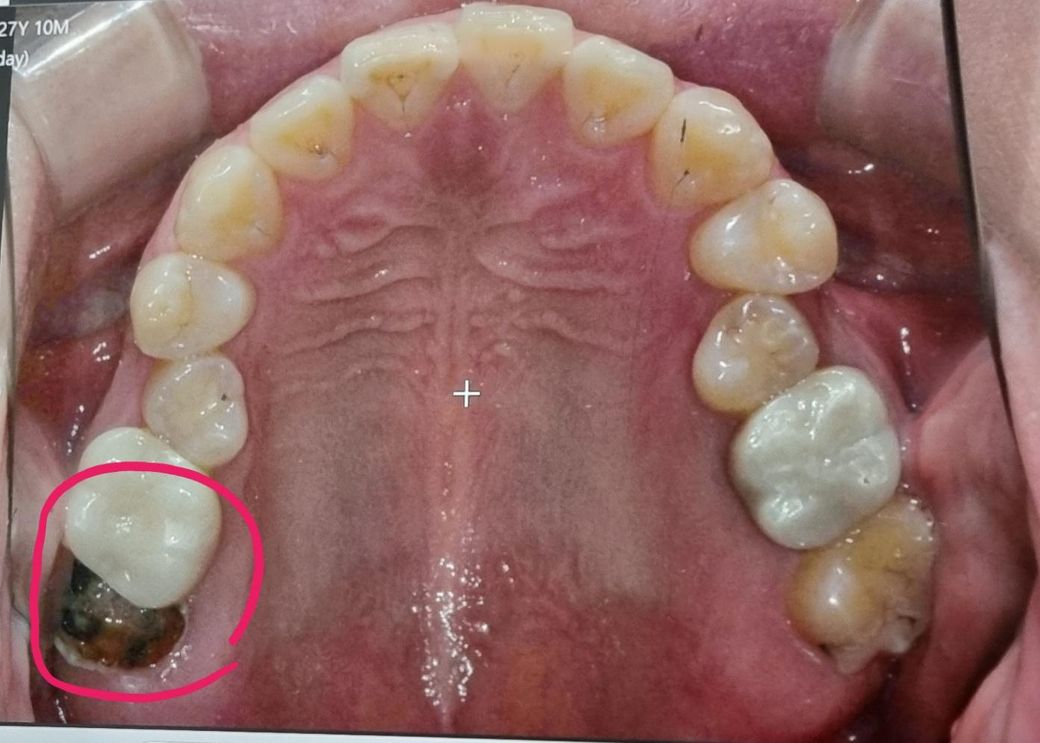

(사진) 꼭 뽑을수 밖에 없는 충치일까요

3번에 걸쳐 깨졌었구요. 한 몇년 방치한겁니다. 너무 무서워요. 뽑고 3개월 지켜본후 임플란트할지말지 결정하라는데 일단 뽑고 고민하는게 맞을ㅋ가요. 치과 더 돌아야하나요

사진상으로 치아 뿌리만 남은거 같으니 저 치아는 발치를 하시는게 맞을것같습니다. 최대한 빨리 발치를 하시는게 좋을것같습니다.

치아가 다 부서져 거의 뿌리 부위만 남은 상태입니다. 저정도는 치아 도저히 살릴 수 없는 상태입니다. 뽑는 수 밖에 없습니다.

지금 치아를 살리는 것은 불가능하며 어느 치과를 가더라도 발치를 해야할 것이라고 말할겁니다.

사진상 맨뒤 어금니 상태는 아주 안좋습니다. 충치가 심해서 다 부러졌고요 아직도 충치균 감염 상태로 뿌리가 남겨져 있을 경우 잇몸뼈도 추가적으로 녹일 수도 있는 상황입니다.

발치하고, 임플란트는 천천히 고민하세요.